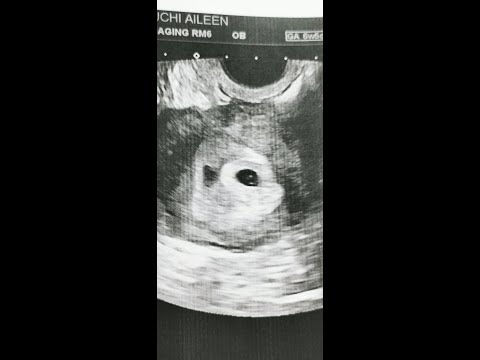

I thought I was 6 weeks , but the dr said I was only 4w 5d . I went back yesterday, and I saw my baby and heard the beautiful heartbeat . I included my two ultrasounds to show you . It's probably just too early for you . I was upset because I know people who posted ultrasound pics of their babies at 5 weeks , so I was sad that mine showed nothing .